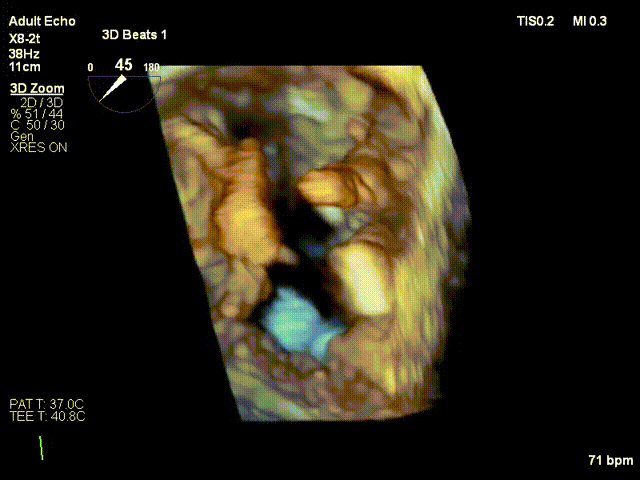

术中鄢华院长团队宋丹主任、郭卉主任与超声科余正春教授经充分沟通及分析,决定术中采用拉链式策略,先在2区偏3区植入1枚短宽二尖瓣夹,术中房间隔穿刺高度:4.2cm,于2区偏3区置入一枚短宽瓣膜降低瓣叶张力、减少撕裂风险,夹闭后瓣叶张力可、夹子L侧仍残余反流2-3+。于是再于2偏1区置入第二枚短宽瓣膜夹,夹闭后反流降至轻度,跨瓣压差1mmHg,肺静脉逆流消失。

于2偏3区置入第一枚短宽夹

调整Orientation至11点50方向

进入瓣下,捕捞瓣叶

瓣叶捕获,Buncing明显

L侧有残余反流

于L侧2偏3区置入第一枚短宽夹

瓣叶捕获

两枚夹子中间有残余反流1+

解离后3D评估组织桥稳定

反流未增加

TMPG:1mmHg

肺静脉逆流消失